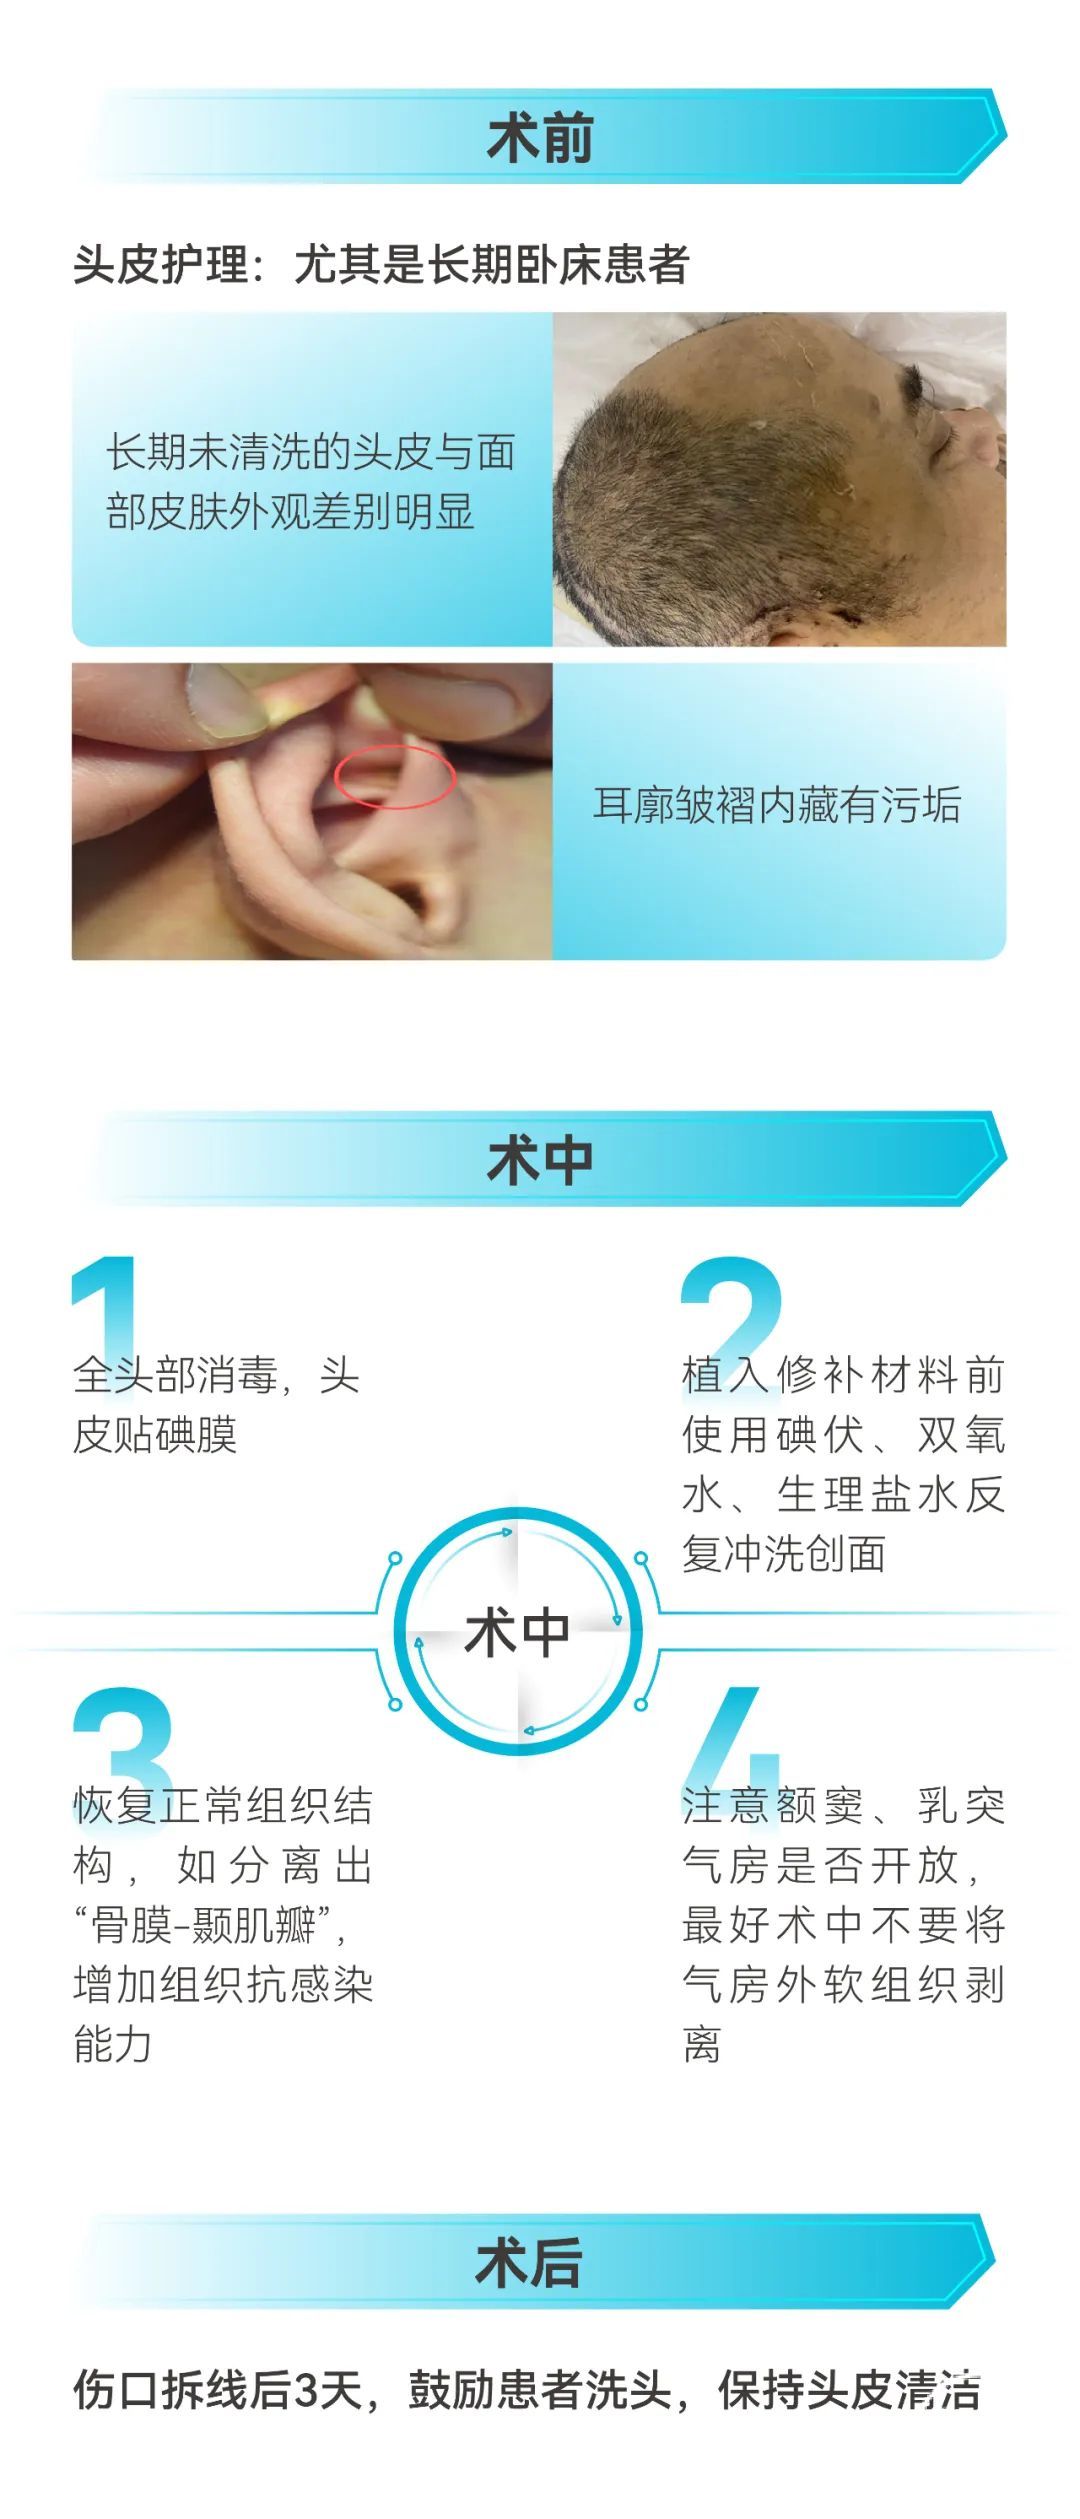

严格无菌操作——包括术前、术中、术后

保护切口血运

严格经原切口切开头皮

尽量减少头皮夹的使用和电烧切口缘的渗血

耳屏前切口注意保护颞浅动脉

头皮缝合可采取皮内缝合

硬膜下积液的预防

术前仔细评估伤口愈合及营养状况;

术中减少电力切割及灼烧创面;

避免暴力牵拉皮瓣,防止静脉回流障碍;

骨窗创面分离时需轻柔,避免硬膜破损;

骨窗边缘尽少分离骨膜,预防渗血增加;

硬膜破损后要及时严密缝合,必要时配合脑膜医用胶或肌肉、筋膜组织+外科胶;

头皮下放置引流管,并接适当的负压吸引,必要时加压包扎创面。